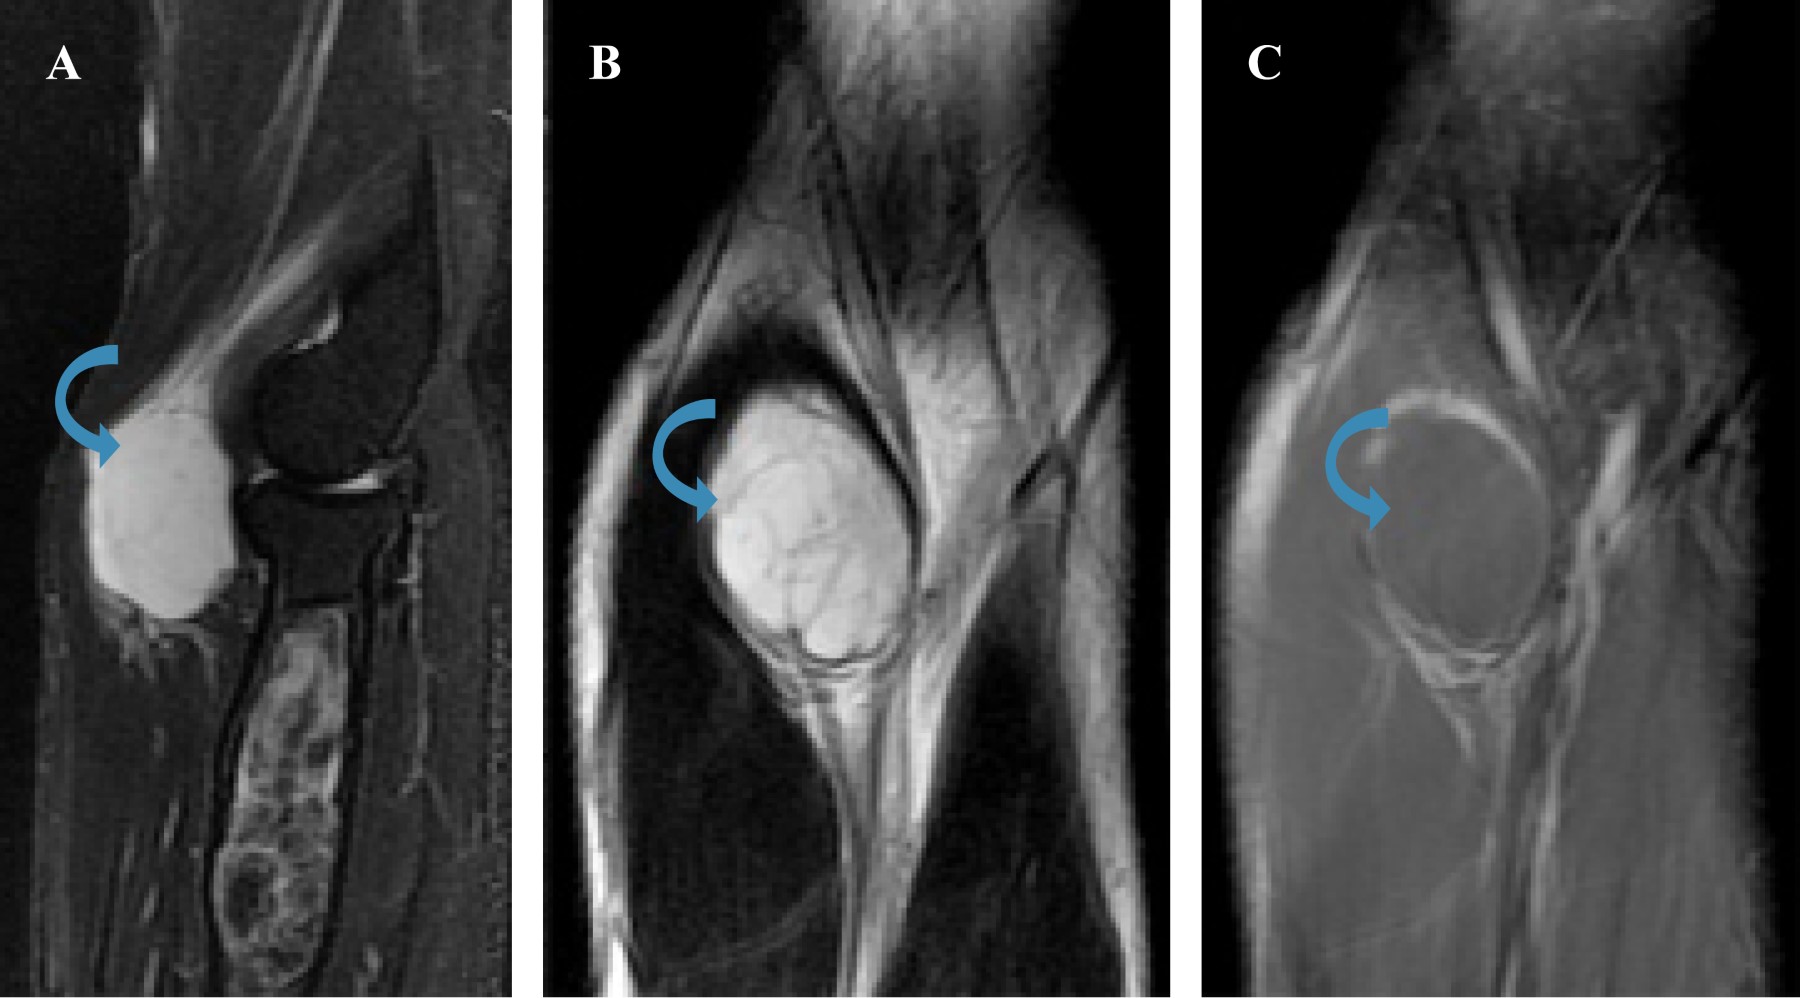

Como parte del abordaje diagnóstico, solicitamos tomografía computada simple y resonancia magnética nuclear simple y contrastada. Por su relevancia, incluimos a continuación las imágenes obtenidas por resonancia magnética nuclear.

En el plano sagital (flecha curveada) se identifica lesión ovoidea, bien delimitada, localizada en los planos musculares de la región anterior del codo, homogénea hiperintensa en STIR. Se observa otra lesión en la región metafisiodiafisaria proximal del radio, la cual es de localización central, zona de transición estrecha con bordes esclerosos, de contenido heterogéneo y predominantemente hiperintensa en STIR (a). En el plano coronal, se observa la lesión de tejidos blandos, la cual es predominantemente hiperintensa con algunas hipointensidades irregulares centrales en T2 (b) y que no presenta realce tras la administración de medio de contraste en la secuencia T1 con saturación grasa (c) (Figura 2).

Figura 2